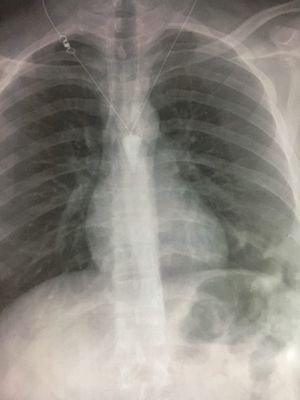

Anyone can tell me why is it a bronchitis? How we see it is a bronchitis disease??

He smokes cigarettes for five years In the winter he has sometimes cough I feel he has mucus in the throat when he sleeps

Ans plz with explanations?? If possible tell how to R/o from other dd's